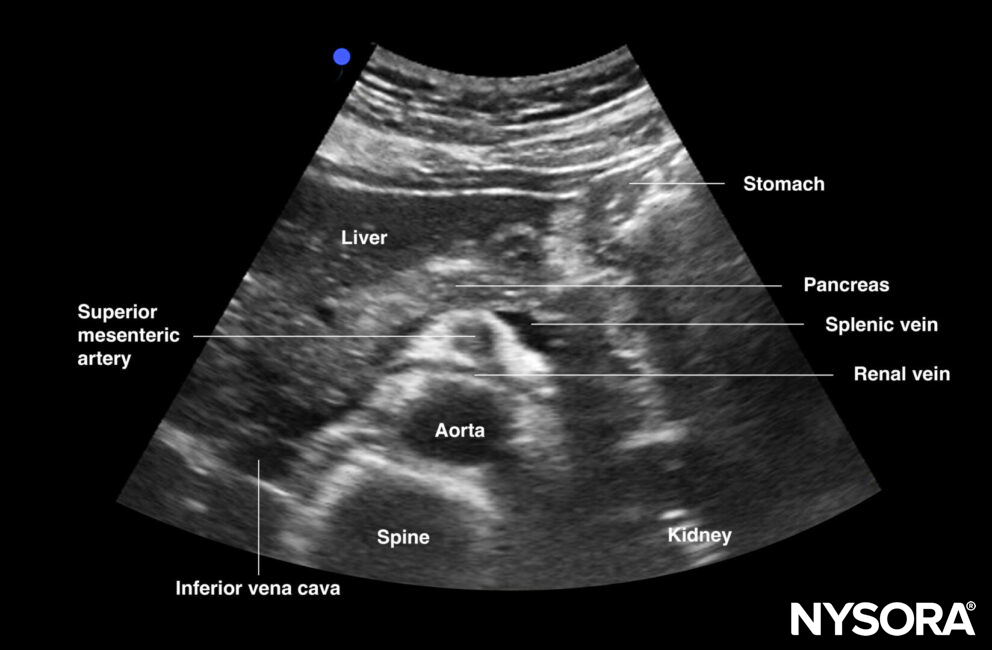

Mid aorta

Transverse view of mid aorta: superior mesenteric artery, aorta, renal vein, splenic vein (anterior to SMA), and left renal vein (between SMA and AA), spine, transverse colon, pancreas, liver

Transverse view of the mid abdominal aorta.